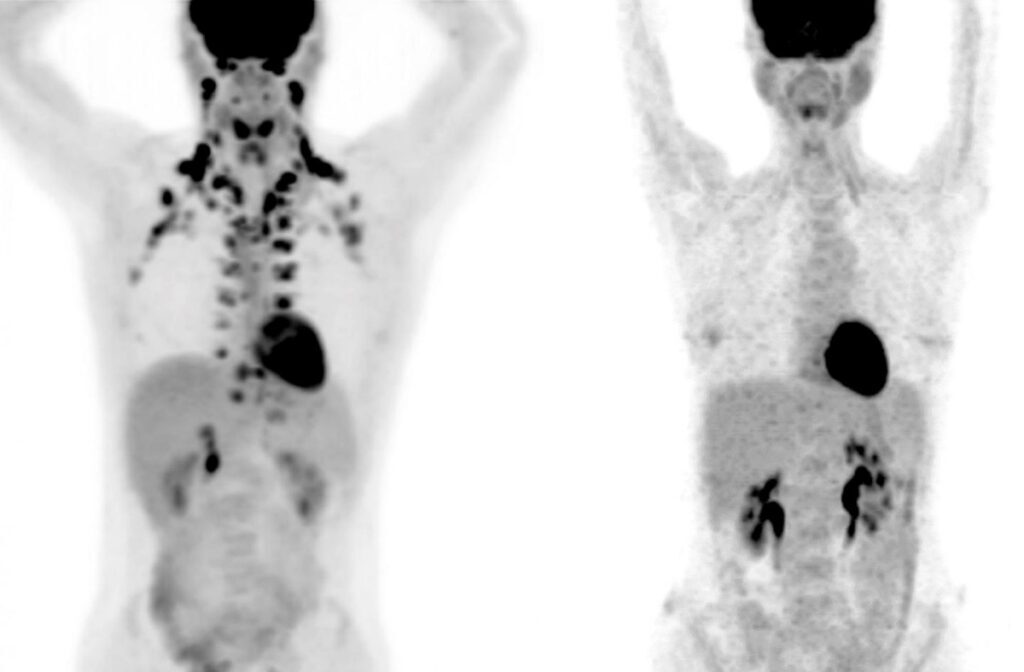

Исследование на 50 тысячах человек раскрыло пользу определённого типа жира в организме человека — бурого. Как оказалось, он снижает риск развития многих заболеваний.